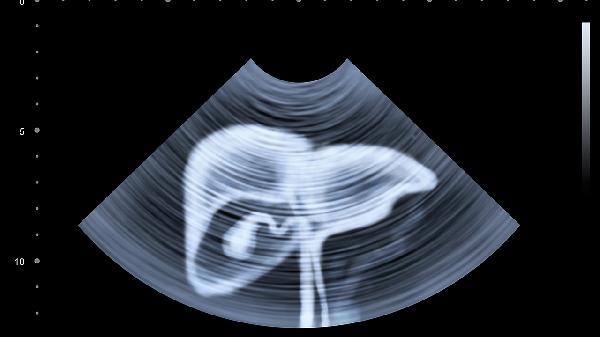

出现上述症状时应及时就医检查肝功能、腹部超声等项目。日常需保持规律作息,避免熬夜和过度劳累。饮食以清淡易消化为主,适量摄入优质蛋白如鱼肉、豆制品,限制高脂高糖食物。严格戒酒,避免使用损肝药物。定期进行肝功能复查,已有肝病患者需遵医嘱规范治疗。适当进行散步、太极拳等低强度运动,保持情绪稳定。